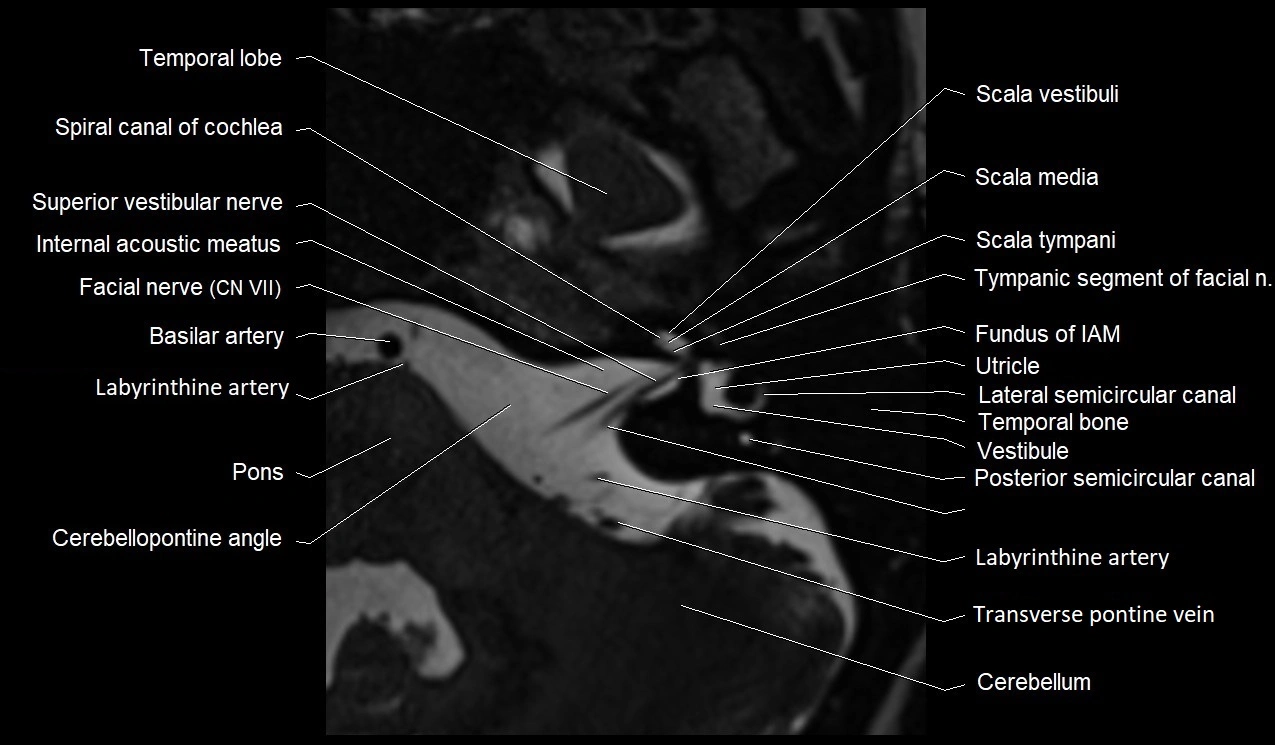

MRI images

image